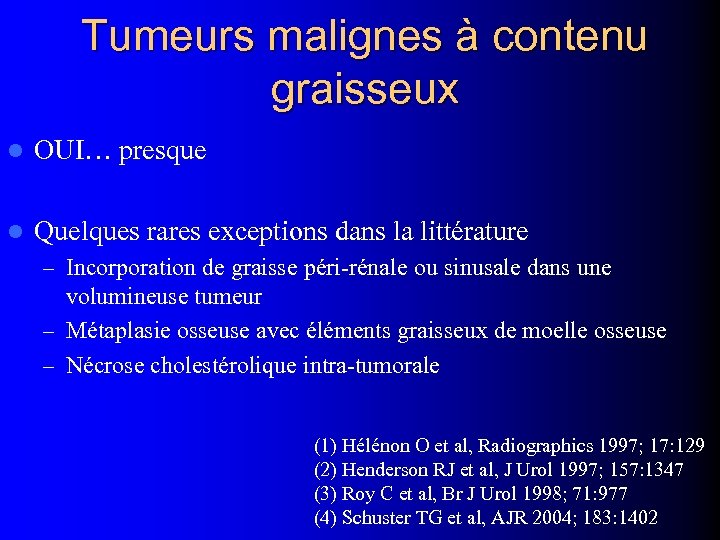

Tumeurs malignes à contenu graisseux l OUI… presque l Quelques rares exceptions dans la littérature – Incorporation de graisse péri-rénale ou sinusale dans une volumineuse tumeur – Métaplasie osseuse avec éléments graisseux de moelle osseuse – Nécrose cholestérolique intra-tumorale (1) Hélénon O et al, Radiographics 1997; 17: 129 (2) Henderson RJ et al, J Urol 1997; 157: 1347 (3) Roy C et al, Br J Urol 1998; 71: 977 (4) Schuster TG et al, AJR 2004; 183: 1402

Tumeurs malignes à contenu graisseux l OUI… presque l Quelques rares exceptions dans la littérature – Incorporation de graisse péri-rénale ou sinusale dans une volumineuse tumeur – Métaplasie osseuse avec éléments graisseux de moelle osseuse – Nécrose cholestérolique intra-tumorale (1) Hélénon O et al, Radiographics 1997; 17: 129 (2) Henderson RJ et al, J Urol 1997; 157: 1347 (3) Roy C et al, Br J Urol 1998; 71: 977 (4) Schuster TG et al, AJR 2004; 183: 1402